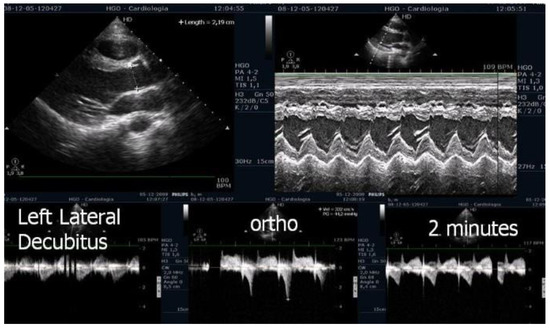

| in [1] | Evaluate IVGs with echocardiography during treadmill exercise and post-exercise in the upright position in patients with HCM. | 17 HCM | Research | Three patients with non-obstructive HCM at rest developed IVGs during exercise. One patient developed this gradient only during orthostatic recovery. The mean IVG in left lateral decubitus (LLD) was 49 ± 4 mm Hg; in orthostatic position it was 62 ± 29 mm Hg (p < 0.001 versus in LLD); at peak exercise it was 83 ± 35 mm Hg (p < 0.001 versus supine rest); during recovery it was 96 ± 35 mm Hg (p < 0.001 versus peak exercise) |